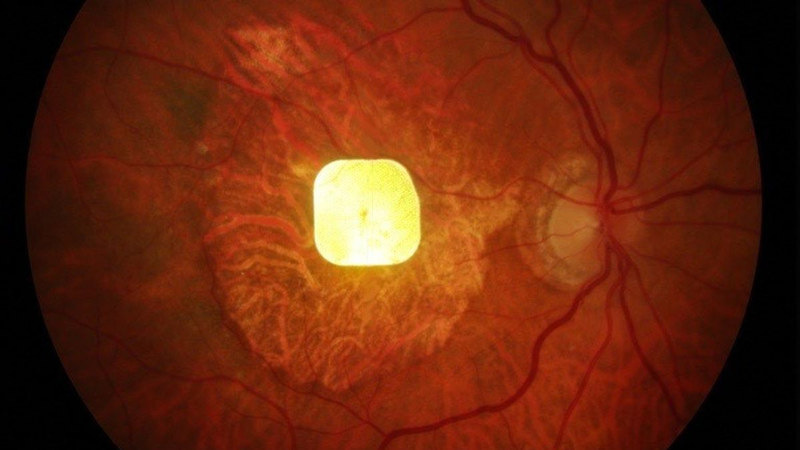

انقلابی در بازگشت بینایی با تراشه چشم مصنوعی

یک تراشه بسیار کوچک که در چشم افرادی با کاهش بینایی ناشی از تحلیل ماکولا مرتبط با سن (AMD) کاشته شده است، برای نخستین بار توانسته بینایی مرکزی آنها را بازگرداند. این سیستم که «PRIMA» ادامه مطلب